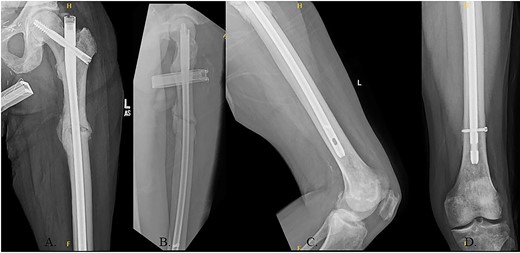

The patient immediately was weight-bearing as tolerated to the operative extremity and worked with physical therapy (PT) to include 80 ft on post-operative day (POD) #2 with use of a front-wheeled walker. He continued to progress with PT and was discharged home POD #8 with home health/PT. At 12 months, the patient denied pain, and XRs demonstrated robust callus formation and bridging healing at the fracture site (Fig. 6).

(A) 12-month post-operative AP radiograph of left hip; (B) 12-month post-operative lateral radiograph of left hip; (C) 12-month post-operative lateral femur radiograph; (D) 12-month post-operative AP distal femur radiograph.